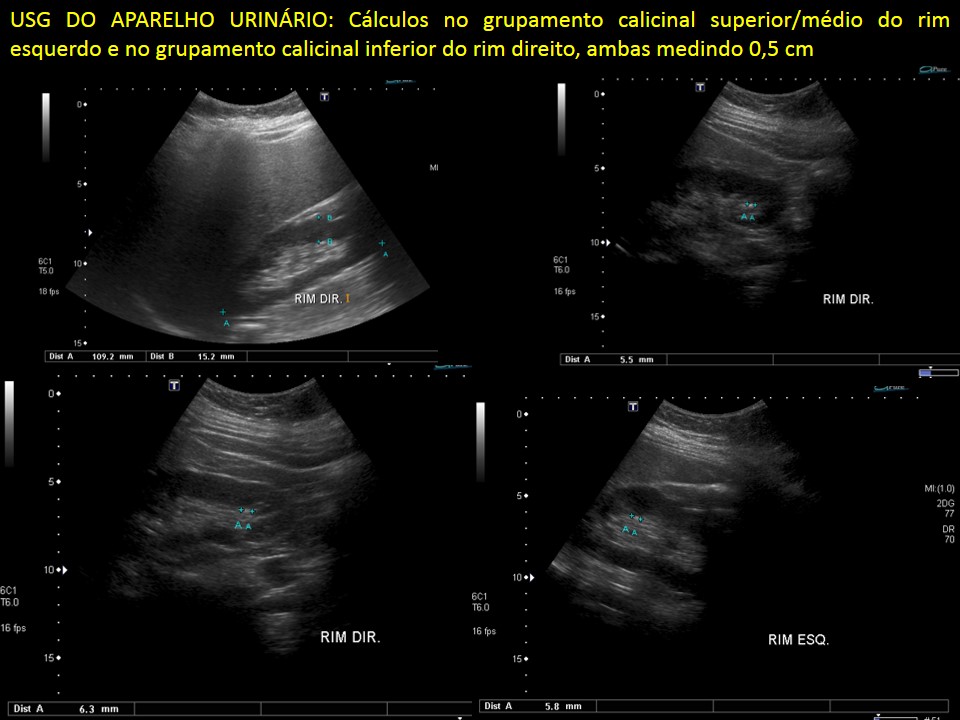

Outra diferença na abordagem da criança com suspeita de cálculos renais é o exame a ser realizado para diagnóstico: enquanto que o melhor exame a ser realizado nos adultos é a TOMOGRAFIA COMPUTADORIZADA de abdome, preferimos inicialmente a realização de um ULTRASSOM DE APARELHO URINÁRIO.

2) FACILIDADE DE LOCALIZAÇÃO DO CÁLCULO: o ultrassom tem como característica a maior definição do diagnóstico quanto menor a distância entre o que se quer observar do aparelho. Como as crianças tendem a ser mais magras e menores, o ultrassom tem maior capacidade de diagnosticar e localizar cálculos urinarios nas crianças.

Nesse contexto inicialmente utilizamos o ultrassom tanto para diagnóstico quanto para planejamento do tratamento dos cálculos nas crianças.